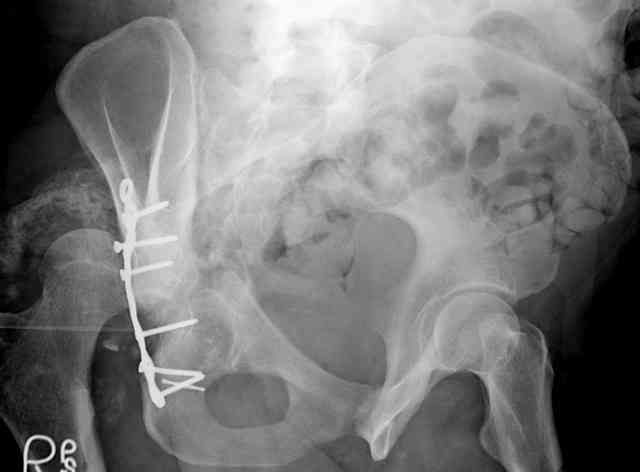

The 2nd example is of a motorcyclist with a transverse fracture-dislocation...he had a closed attempted reduction and placed in traction but the manipulative reduction was not concentric (not unusual for this injury pattern)...so the traction was adjusted to be just enough to disengage the head from the fracture (12#) until he could be cleared for surgery one day after injury...he was treated "urgently" then with a prone KL, clean the fracture, reduce and clamp it, screw it, support with a balanced plate, close, and enjoy...2-3hours, 400cc EBL, blah, blah, blah..